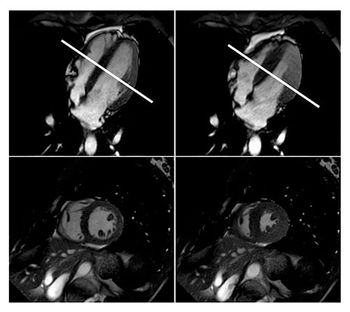

CHICAGO-MRI suggests that subclinical cardiac dysfunction could be indicative of early brain disease.

CHICAGO-MRI shows significant changes to the heart of elite free divers.